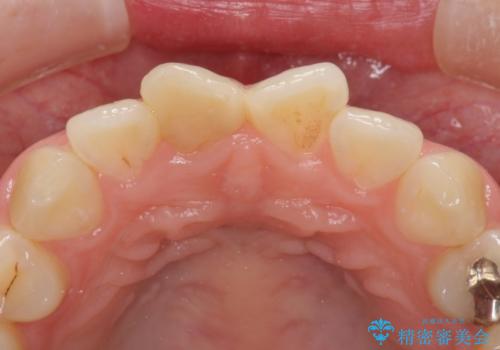

根管治療について

保険根管治療は回数がかかることが多く、終了予定がわかりにくいです。

当院では、根管治療は長い時間のご予約を頂き、多くの場合2~3回で終わります。

根管治療は歯内の治療なので患者様には見えない場所ですが、ここが細菌で汚染されると激しい痛みや長引く違和感の原因になります。

当院では、清潔な治療を徹底し、顕微鏡を使用した精密な治療を行っています。

症状や根管の状態により、治療金額が異なります(5~10万円目安)。治療回数による費用負担の増減はありません。